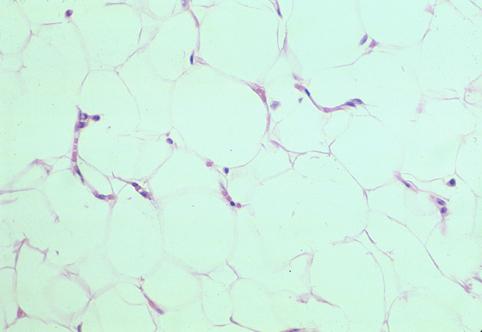

Lipoma del Colon extirpado conjuntamente con Cáncer de Colon

[Image-ID:2825]

Tumor no Epitelial Benigno/Lipoma

colon/transverso

Micro

10 - 14